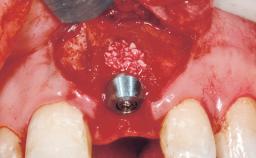

A 30-year-old female patient had lost tooth 21 and was referred to our clinic for consultation and treatment. Due to advanced apical infection, tooth 21 had been extracted two months earlier at another clinic and an acrylic-resin tooth had been bonded to the adjacent teeth. The patient desired implant treatment to avoid any damage to the adjacent natural teeth. While the patient had no history of any systemic disorder, she was a heavy smoker and exhibited medium to advanced periodontitis in the entire jaw. After the initial treatment to achieve a pocket probing depth of less than 4 mm and no bleeding on probing, a decrease in the height of the papillae mesial and distal to the extraction site and overall gingival recession were observed.

Bone Augmentation Horizontal|Staged

Augmentation Materials Autogenous chips|Membrane

Soft Tissue Grafting Simultaneous

Bone Volume Deficient horizontally, requiring prior grafting